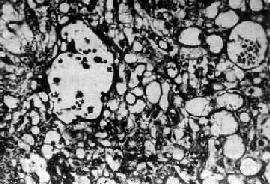

图13-22 卵巢囊性畸胎瘤 囊内充满含有毛发的黄色油脂样物 囊性畸胎瘤预后好,少数可发生恶性变,最常见者恶变为鳞癌。恶性变常发生在囊壁内头节附近,故检查时应注意取材部位。 2.未成熟型畸胎瘤(teratoma,immature type)此型较少见,仅占卵巢畸胎瘤的1%~3%。多见于25岁以下的年轻患者。 【病变】 肉眼观,肿瘤多为单侧性,体积一般较大,结节状,切面多为实性,夹杂有单个或多个大小不等的囊性部分。实性部分常为杂色,灰白、棕色或黄色,质软而脆,常有出血坏死。镜检可见由三胚层分化而来的未成熟和成熟组织混合组成。常见的未成熟组织为神经组织,如原始神经上皮和室管膜等结构及各种胚胎性组织,如胚胎性骨、软骨及肌肉等。皮肤组织较成熟型少见。其中可混杂一些各胚层的成熟组织。 未成熟型畸胎瘤常合并其他生殖细胞肿瘤,如内胚窦瘤、无性细胞瘤及绒癌等。一般说,肿瘤组织中未成熟组织及胚胎性组织的含量与临床恶性程度有关。病理上根据未成熟组织的含量,可分3级:①1级,主要为成熟组织,有少量未成熟组织,没有神经上皮或每一切片中神经上皮不超过一个高倍视野;②2级,有较多未成熟组织,每一切片中所含神经上皮不超过1~3个高倍视野;③3级,未成熟组织量多,每一切片中神经上皮超过4个高倍视野。 预后 未成熟畸胎瘤的预后与病理分级、临床分期密切相关。复发及转移者多为2、3级。转移的部位多在盆腔及腹腔内,远处转移极少。 (二)无性细胞瘤 无性细胞瘤(dysgerminoma),较少见,约占卵巢恶性肿瘤的1%~2%,多见于10~25岁年轻妇女。 【病变】 肉眼观,常为单侧性,约10%为双侧性。肿瘤多为圆或卵圆形,表面光滑,质韧。切面多为实性,有不同程度的出血坏死或囊性变,色灰红、暗红及棕黄色。镜下,与典型的睾丸精原细胞瘤非常相似,瘤细胞体积大而圆,比较一致,胞浆因含糖原而透明。核大,圆或卵圆形,大小形态一致,小泡状,核仁明显,核分裂像常见。瘤细胞排列成片块、巢状或条索。瘤细胞间常有不等量的淋巴细胞浸润及多少不等的纤维组织。由于肿瘤细胞形态和组织化学特性与未分性别的原始生殖细胞极相似,故命名为无性细胞瘤。 本瘤预后较好,对放射线敏感,5年生存率90%~95%。约5%病人对侧卵巢在显微镜下才能发现肿瘤,因此手术时必须进行活检,作冷冻切片检查。 肿瘤可直接蔓延扩散至盆腔附近器官及通过淋巴系播散到腹膜后及主动脉旁淋巴结等,晚期也可经血行播散到肺及肝等。 (三)内胚窦瘤 内胚窦瘤(endodermal sinus tumor)又称卵黄囊瘤(yolk sac tumor),来源于多能的生殖细胞,向胚外结构方向分化而形成的一种高度恶性的生殖细胞肿瘤。多见于儿童及年轻妇女,平均年龄18岁。除卵巢外,还可发生于骶尾、腹膜后、纵隔、松果体等处。 【病变】 肉眼观,肿瘤多为单侧性,以右侧为多,一般体积较大,平均直径为15~25cm,圆或卵圆形,表面光滑。切面多为实性,质较脆,灰白或粉白色,常有出血坏死及囊性变。镜检,组织形态较复杂及特殊,主要特征有下列几点:①网状结构,是最常见的形态,由星芒状的瘤细胞形成疏松网状结构(图13-23),其中有微型小囊或间隙,囊腔被覆扁平或立方细胞,这种结构类似胚外中胚层结构;②内胚窦样结构,立方或柱状的瘤细胞成单层排列,包绕毛细血管,形成一血管套样结构,这种结构横切面很像肾小球,称为Schiller-Duval小体,这种小体和大鼠胎盘内的Duval内胚窦结构相似,这种结构可能是由卵黄囊衍生演变而来;③多泡性卵黄囊样结构,特征是由扁平上皮、立方或低柱状的瘤细胞形成大小不等的囊腔,其间隔以致密的结缔组织或疏松的粘液样间质,这种结构与胚胎时期的卵黄囊(胚外内胚层)相似;④在瘤细胞内及瘤细胞间隙可见PAS阳性的大小不等的嗜酸性小滴,免疫组化显示这种小滴含有甲胎蛋白(AFP),正常情况下,卵黄囊可合成AFP;⑤可见腺样、乳头状及实体细胞团结构等。

图13-23 内胚窦瘤 呈疏松网状粘液瘤样结构,其中有互相沟通、衬以上皮的腔隙及小囊腔,在瘤细胞内外可见嗜酸性玻璃样小球及基底膜样物 本瘤恶性度很高,预后差,对放射线不敏感。近年应用联合化疗后,3年存活率约13%。转移途径为直接浸润及种植扩散,偶有淋巴结转移,极少血行转移。 (四)胚胎性癌 胚胎性癌(embryonal carcinoma)为来自具有向胚外或胚内结构分化潜能的原始生殖细胞的一种未分化癌。较罕见,约占卵巢恶性生殖细胞瘤的5%。多见于儿童及青年,平均年龄为15岁。 【病变】 肉眼观,肿瘤一般为单侧性,体积较大,平均直径17cm,实性。切面棕褐或灰白色,常见出血坏死及囊性变。镜下,瘤细胞为大而幼稚的多形性细胞,胞浆中性呈不同程度的空泡状。核大而圆,空泡状,染色质粗,核仁明显,1至多个,核分裂像多见。瘤细胞排列呈实性巢状或腺泡、管状或乳头状,并常见散在的像合体滋养层细胞的多核巨细胞。免疫组化染色显示这种巨细胞含有绒毛膜促性腺激素(HCG),非巨细胞性瘤细胞内含有甲胎蛋白。 本癌为高度恶性,预后差,早期即可向局部器官和腹膜浸润,或通过淋巴道播散。5年存活率39%。